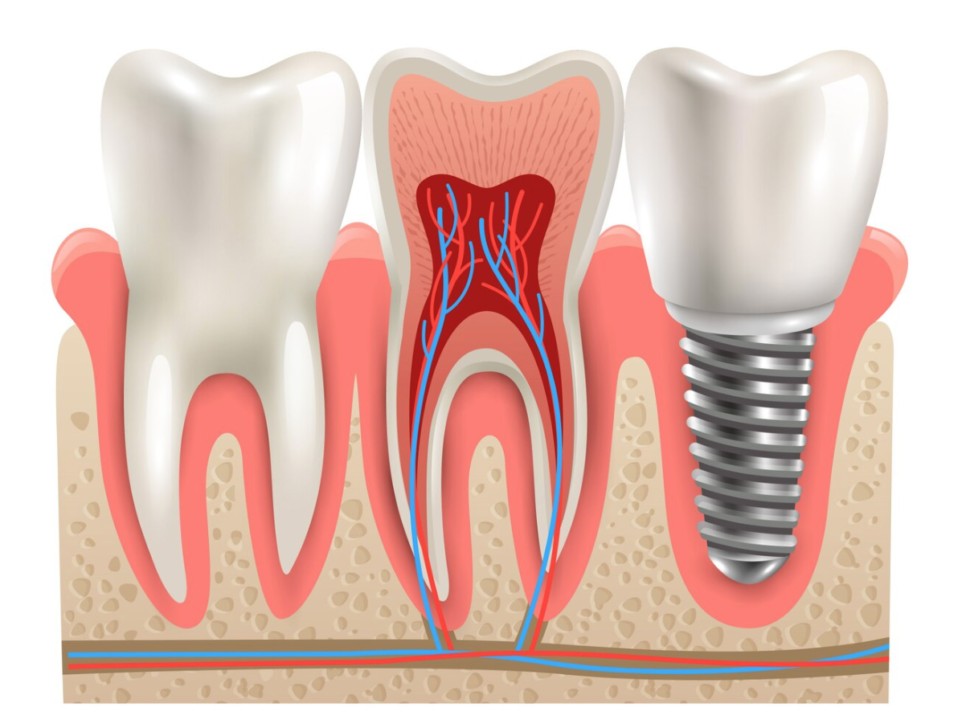

- Implant Center: Restore your smile and confidence with our state-of-the-art dental implant solutions. Our implant center offers durable and natural-looking replacements for missing teeth, improving both function and aesthetics.

- Root Canal: Preserve your natural teeth and relieve discomfort with our expert root canal therapy. Our skilled team uses advanced techniques to treat infected or damaged tooth pulp, restoring health and function.

Dental Implant Center

Are you ready for your perfect Smile? Our Implant Center offers a high-tech approach using technology for dental excellence ...

Root Canal

Experience the future of pain-free dentistry with our high-tech root canal treatments, ensuring comfort and expertise from o ...